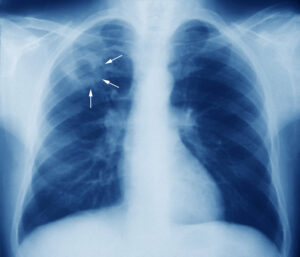

Namibia remains in the top 10 countries globally, with many TB cases.

Namibia currently carries one of the highest burdens of TB and multi-drug resistant TB globally.

A 2020 study has found that the country has a rate of 442 cases per 100 000 people and is ranked fifth among countries with the highest TB burdens.